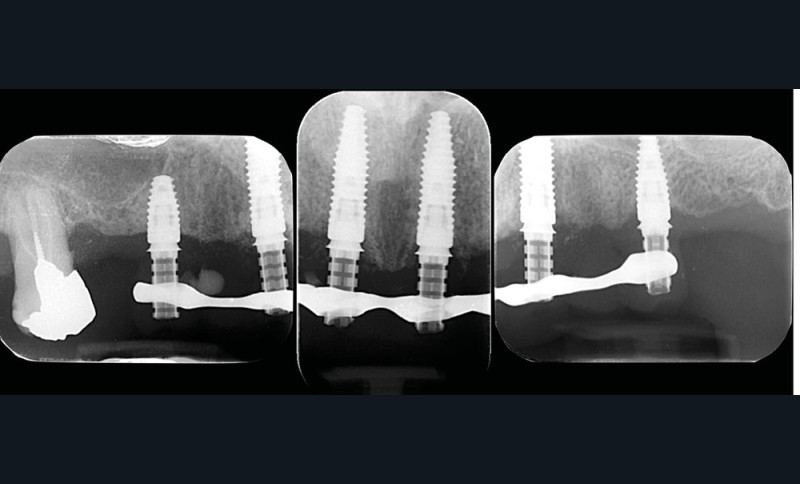

Après une étude prothétique [4, 5], il est décidé de procéder à l’extraction des dents maxillaires résiduelles (sauf une molaire qui servira pour enregistrer l’occlusion et qui sera avulsée dans un second temps), avec une implantation immédiate de 6 implants maxillaires et une mise en charge immédiate d’un bridge provisoire. Les implants se distribuent sur l’arcade ; des aménagements sous-sinusiens ne sont pas nécessaires (fig. 4 à 6).

Des implants mandibulaires postérieurs sont également programmés dans la même séance.